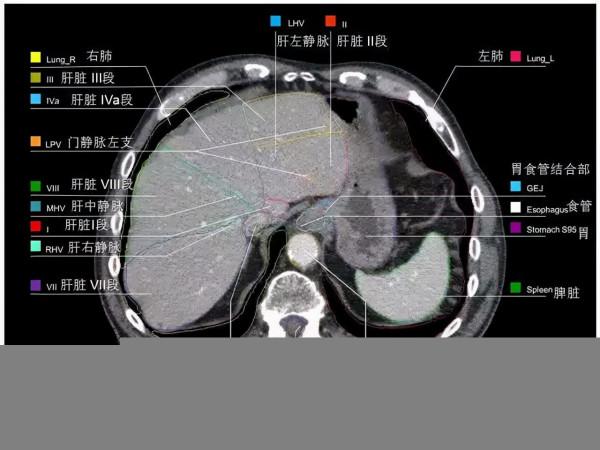

心臟

冠脈解剖:

後降支posterior descending branches PD

左室後支 posterior branches of leftventricular PL

銳緣支 right marginal branch AM

右圓錐支 right corus artery CA

右室前支 right anterior ventricular branches

右房動脈 right atrial artery

左冠狀動脈

左主幹 left main coronary artery LM 或LCA

前降支 left anterior descending branch LAD

對角支 diagonal branches 或左室前支 left anterior ventricular branches

前間隔支 anterior septal artery

左圓錐支 left corus artery LCA

左迴旋支 left circumflex branch LCX

鈍緣支 obtuse marginal branch OM

左室前支 left anterior ventricular branches

左室後支 left posterior ventricular branches

左房支 left anticular branches

Maximum intensity projection (MIP)